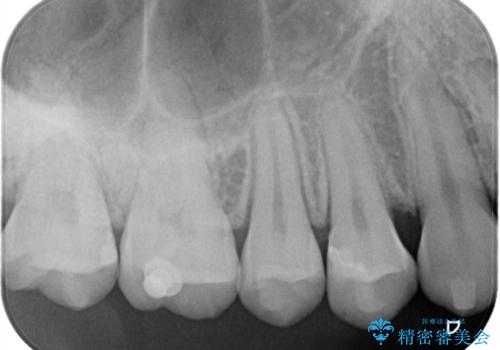

【セラミックインレー】歯と歯の間の虫歯治療

- 歯と歯の間に虫歯が見つかったため、拡大鏡を使用して丁寧に虫歯を除去し、セラミックインレーにて修復治療をおこないました。

セラミックインレーはレジン(プラスチック)と違い、形態の付与がしやすく、長期的な安定性が高い治療です。